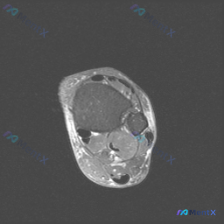

怀疑足踝软组织积液,但T1 MRI全阴性?这个陷阱很多人踩过

这是一张足踝部MRI-T1加权轴位影像,扫描层面位于踝关节近端(小腿远端),我们先梳理一下影像上的明确发现:

- 骨骼结构:胫骨、腓骨骨皮质连续,未见骨质破坏;骨髓信号均匀,符合正常黄骨髓表现,没有局灶性异常信号

- 软组织与肌腱:各个肌腱走行、信号正常,没有增粗或中断;肌肉组织信号均匀,没有萎缩或脂肪浸润;皮下脂肪与筋膜层次清楚,没有明显肿胀

- 血管区域:主要血管束走行正常,没有占位或异常信号